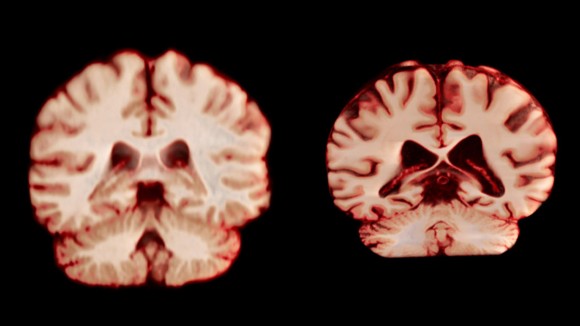

Sydney, Australia - Penelitian terbaru menunjukkan bahwa pria mengalami penurunan volume otak yang lebih besar dan di lebih banyak area dibanding wanita saat menua. Studi ini dilakukan dengan menggunakan pemindaian MRI terhadap ribuan peserta sehat tanpa gangguan kognitif, untuk memahami bagaimana otak berubah selama proses penuaan.

Wanita secara signifikan lebih sering didiagnosis dengan Alzheimer, sehingga para ilmuwan berharap menemukan hubungan antara penurunan otak terkait usia dengan risiko penyakit ini. Namun, hasil penelitian menunjukkan bahwa pria yang mengalami penurunan volume otak lebih besar, terutama di beberapa bagian penting otak.

Salah satu area yang menunjukkan perbedaan adalah postcentral cortex, bagian otak yang memproses sensasi seperti sentuhan dan rasa sakit. Penurunan volume di area ini terjadi sekitar 2,0% tiap tahun pada pria, sedangkan pada wanita sekitar 1,2% tiap tahun. Hal ini menunjukkan pria mengalami penuaan otak yang lebih cepat.

Para peneliti menjelaskan bahwa meskipun pria memiliki penurunan volume otak yang lebih cepat, hal ini tidak menjelaskan kenapa wanita lebih rentan terhadap Alzheimer. Faktor lain, seperti perbedaan dalam kemampuan bertahan hidup atau kerentanan biologis, mungkin memegang peran penting dalam perbedaan prevalensi tersebut.